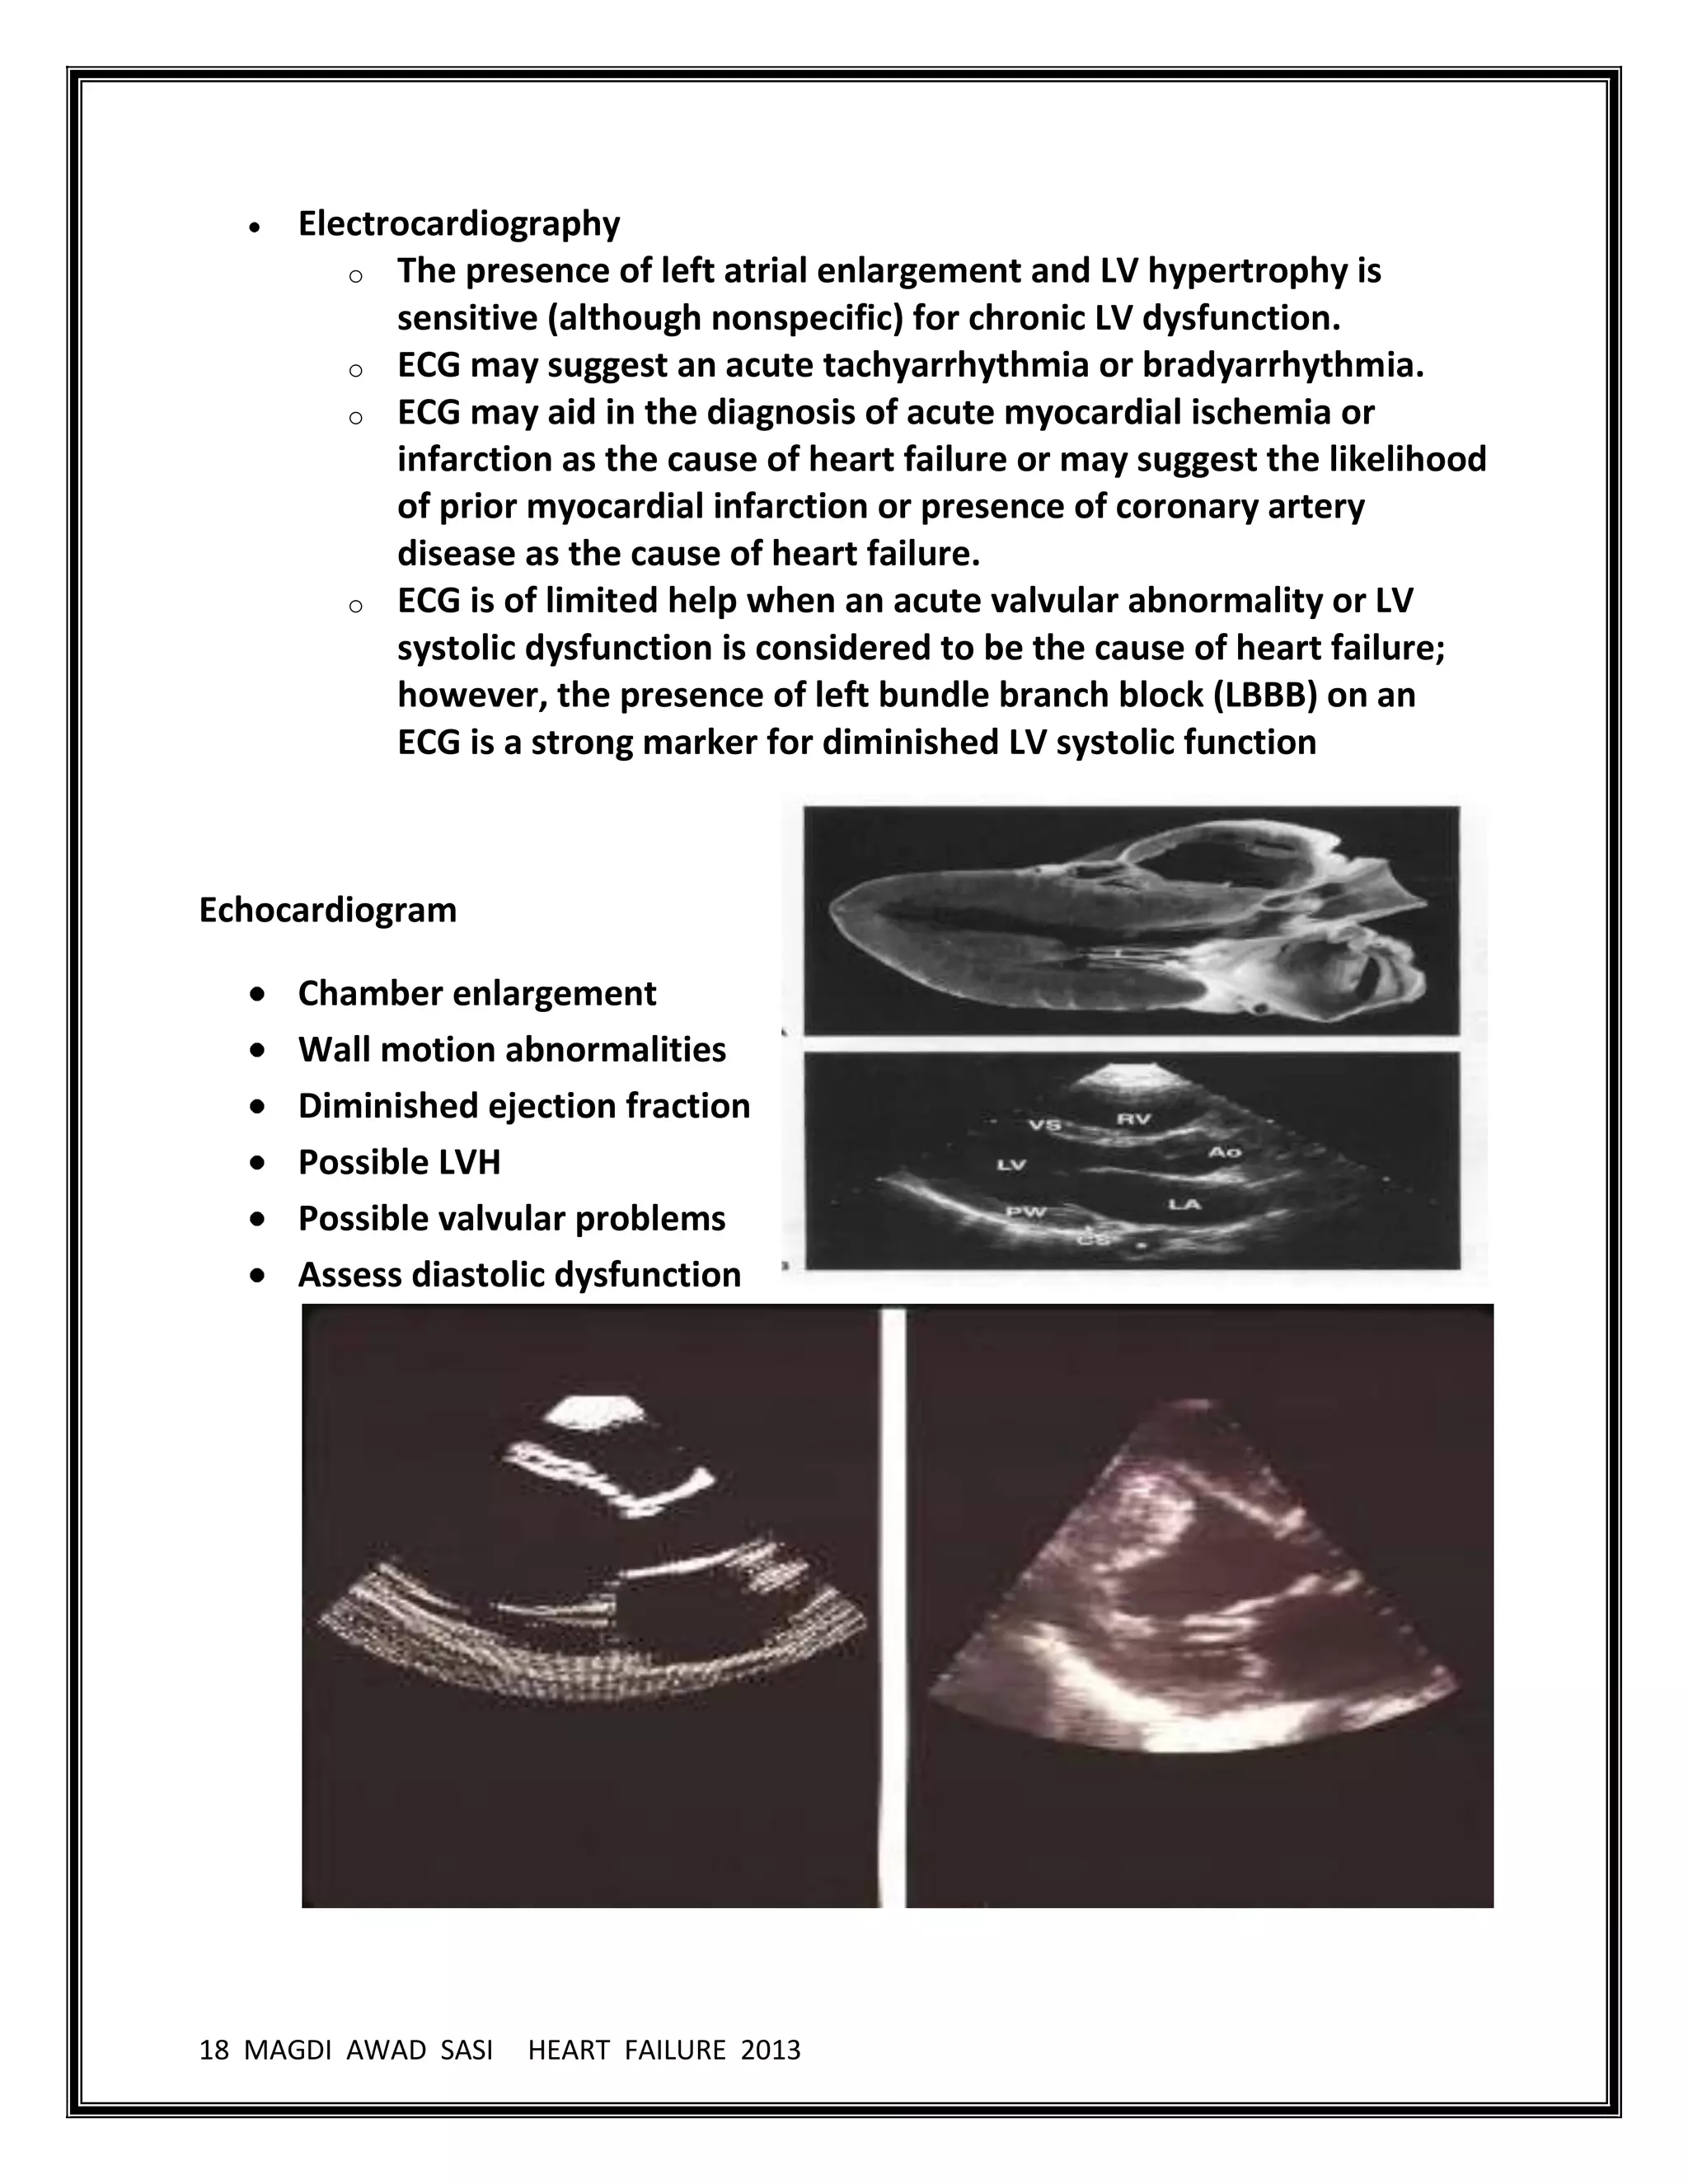

Chest radiographs in patients with abrupt onset are usually helpful but can be

limited because a delay of as long as 12 hours is possible from the onset of

dyspnea due to acute heart failure to the development of classic abnormal

findings on radiographs.

Classic radiographic findings demonstrate cardiomegaly (in patients with

underlying CHF) and alveolar edema with pleural effusions and bilateral

infiltrates in a butterfly pattern. The other signs are loss of sharp definition of

pulmonary vasculature, haziness of hilar shadows, and thickening of

interlobular septa (Kerley B lines).

In long standing biventricular chronic heart failure, chest radiographs may only

show cardiomegaly without alveolar edema or pleural effusions due to

adaptive lung mechanism with increased arterial vasoconstriction and

lymphatic drainage.